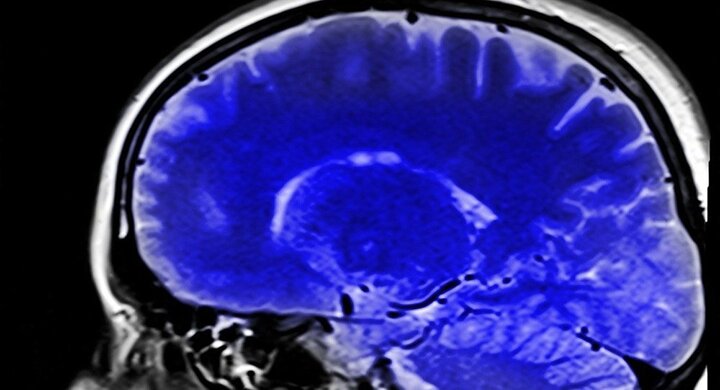

Các nhà khoa học từ đại học Standford phát hiện ra một loại protein có thể là nguyên nhân gây nên tình trạng lão hóa sớm ở não bộ, gọi là VCAM1.